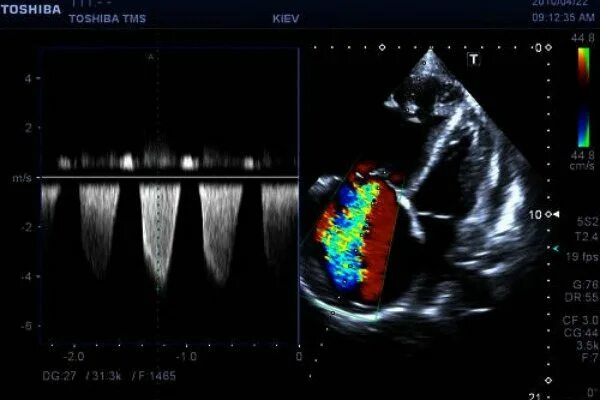

Эхокг сдла